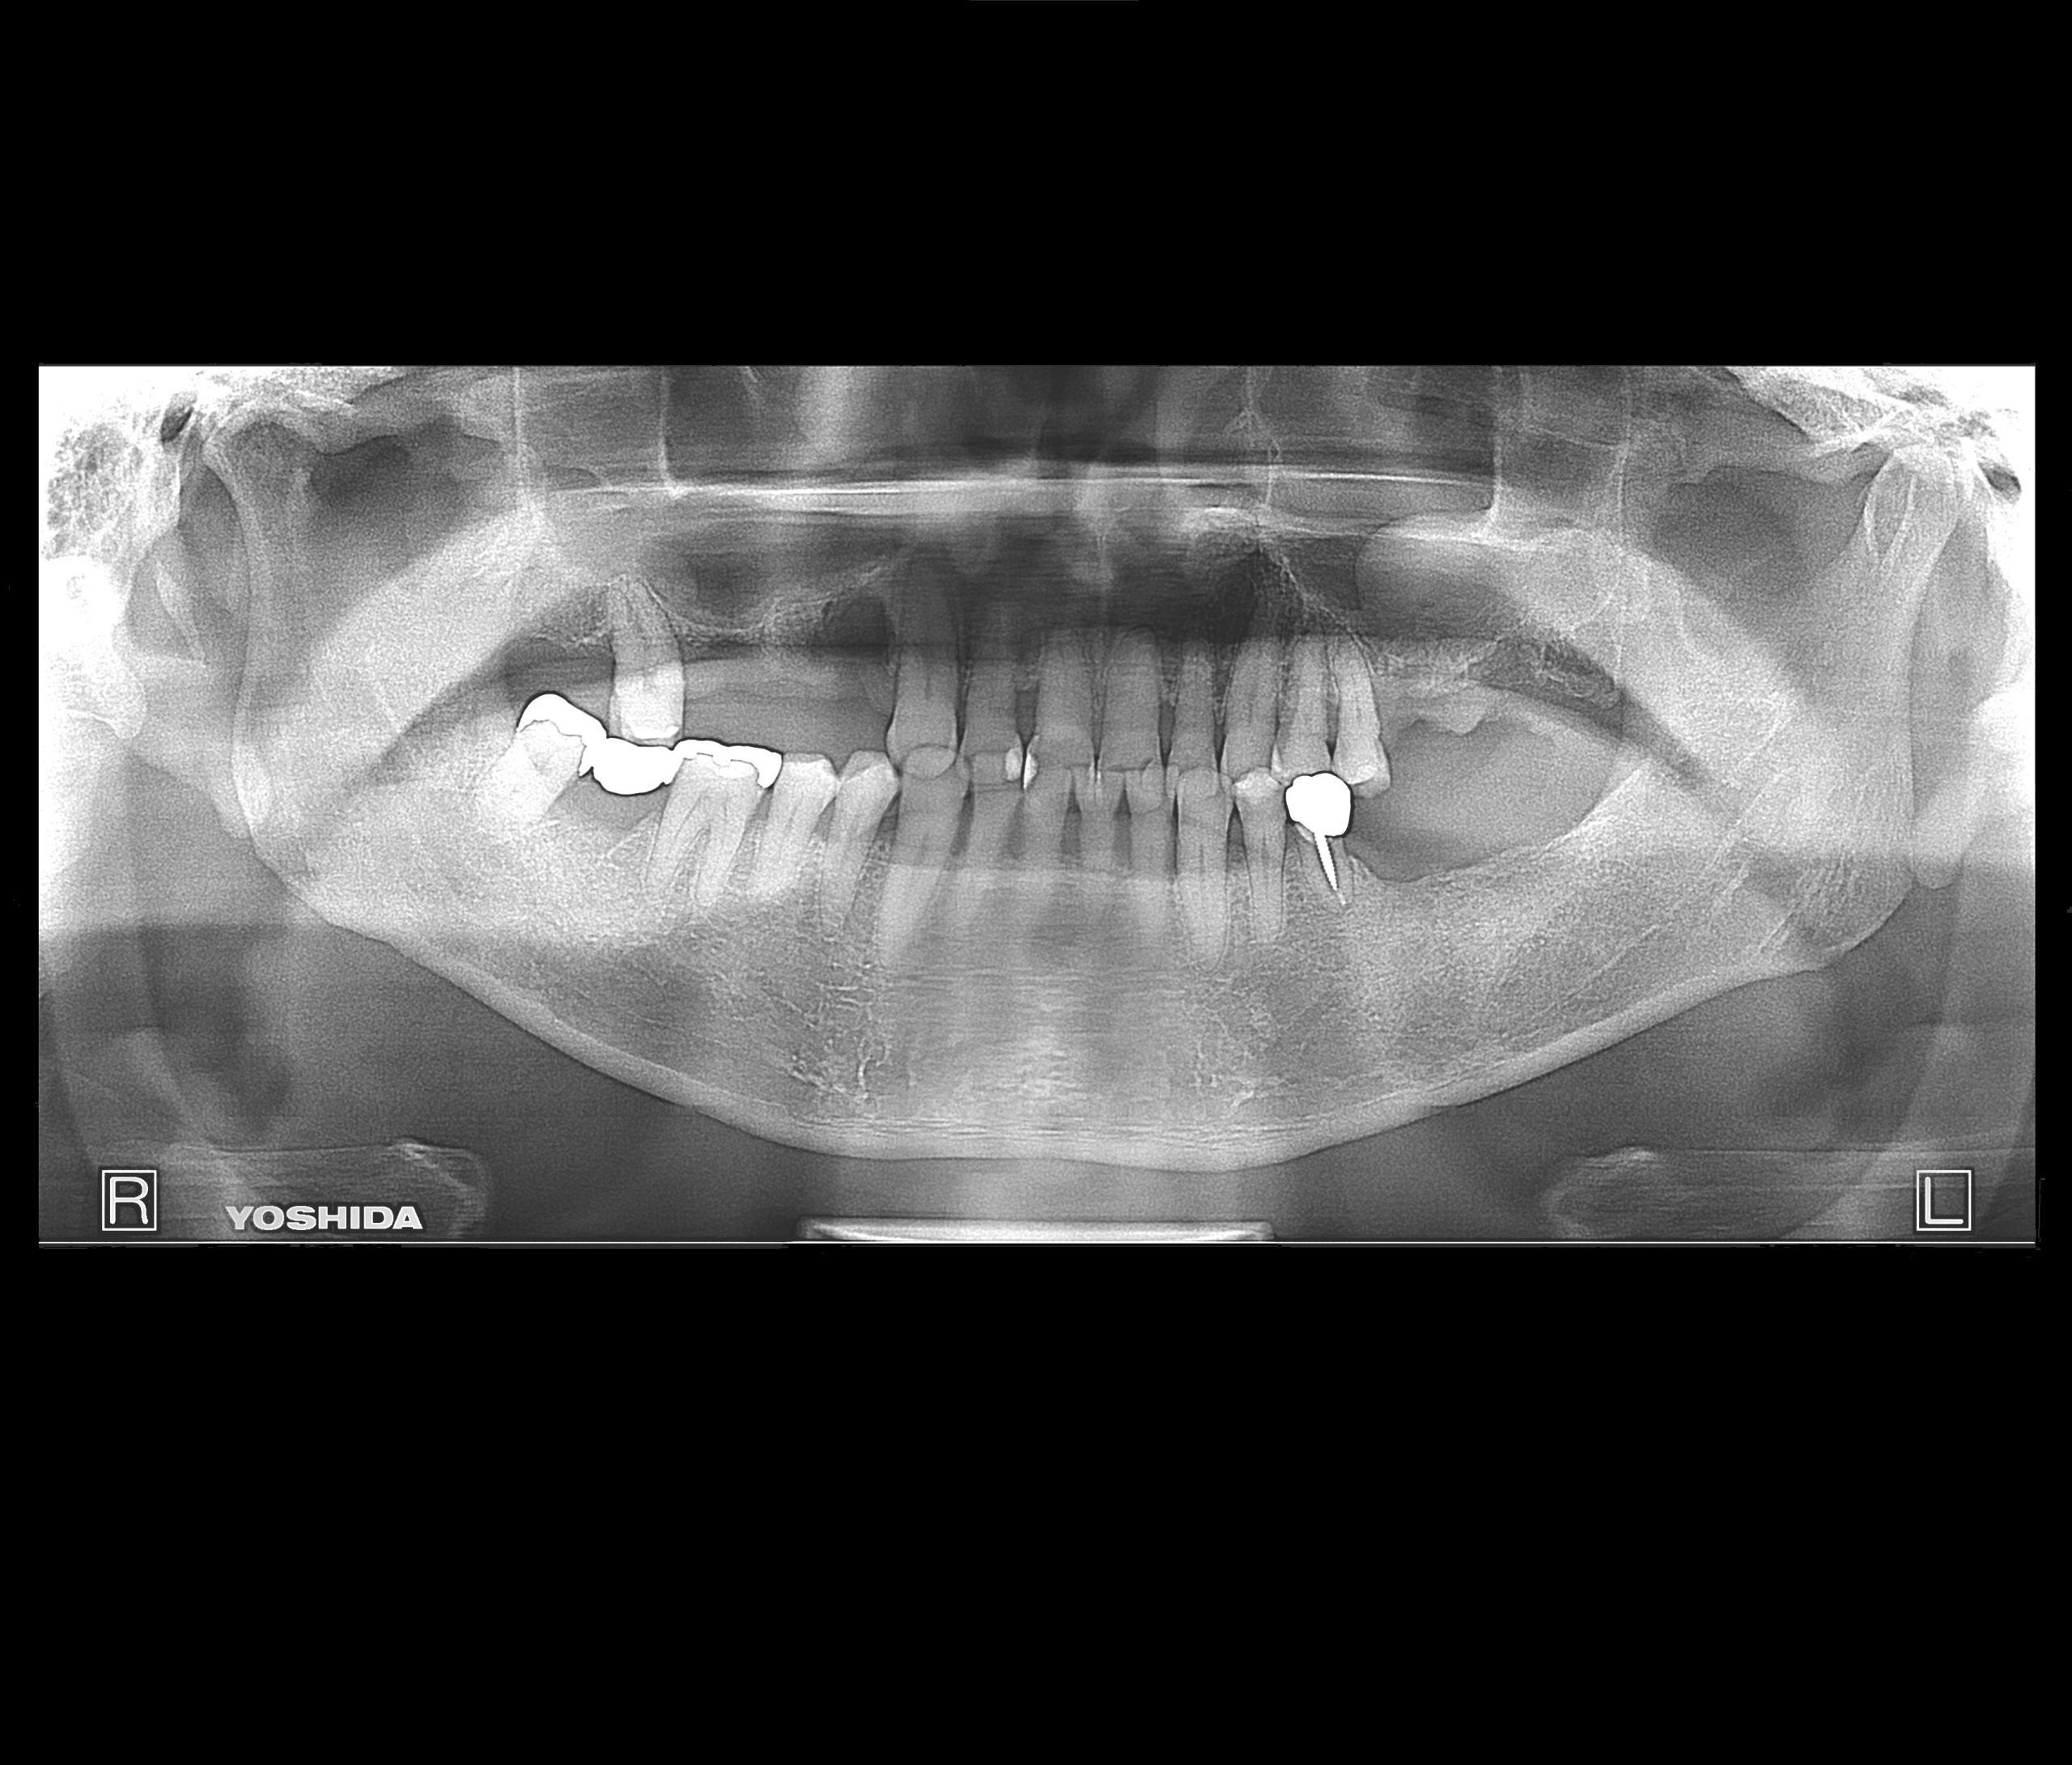

症例230代 男性 左上5 副鼻腔膜を挙上しインプラントを埋入

治療前

治療後(1年経過)

※説明

主訴 根尖病巣を長期放置していた為、抜歯。年齢を考慮し、インプラントを選択。

骨高不足の為、ソケットリフト(骨造成)を採用。

採血により得たCGFメンブレンとAFGブロック(人工骨β-TCPとAFGを混ぜたブロック)を填入し、副鼻腔の洞底膜を6㎜挙上後、インプラント体を埋入。

約4ヶ月間の免荷期間を経て、ジルコニアを装着。

リスクとしては、外科的侵襲がある。デメリットは、保険外診療の為、経済的負担がある。

費用 69万(税込)(オペ・ソケットリフト・人工骨・採血による濃縮血小板生成・仮歯・最終補綴物まで含む)